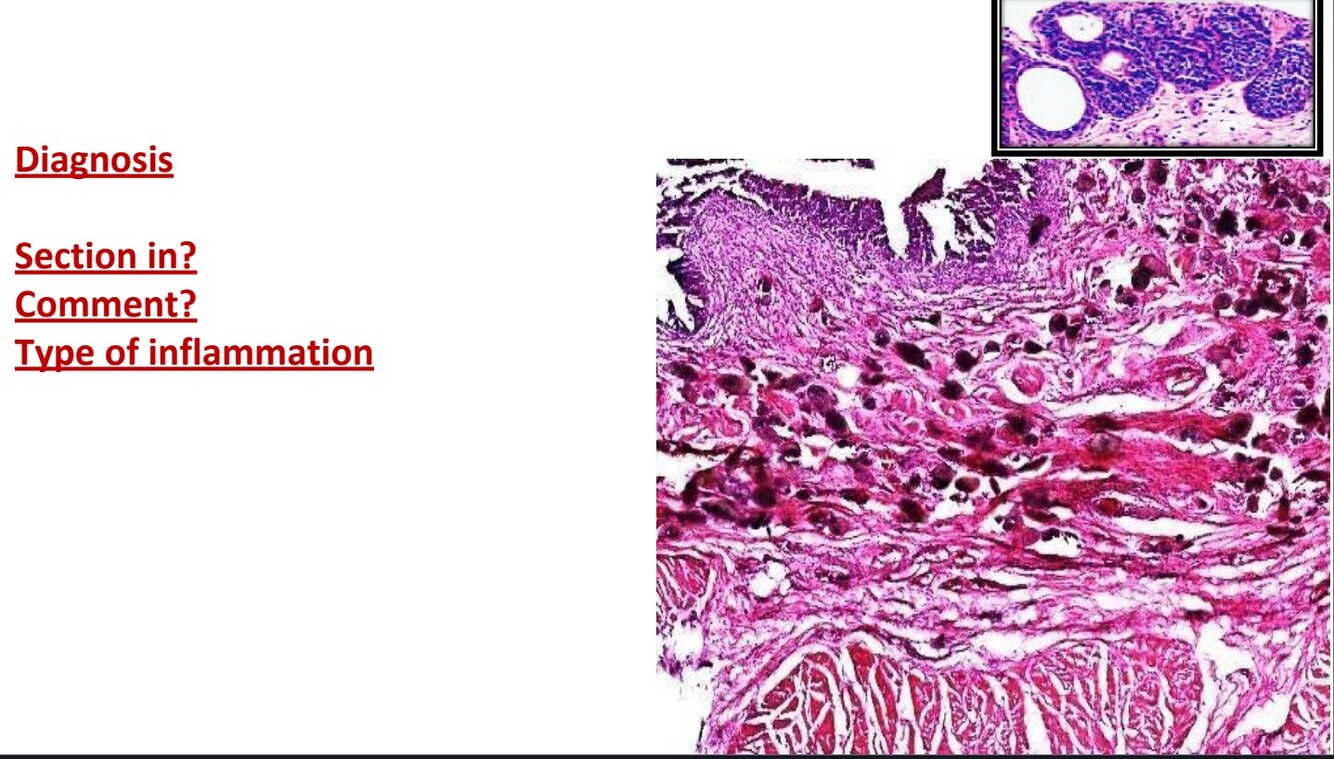

Acute suppurative appendicitis

The mucosa, submucosa show edema, congested capillaries and exudate

Lumen of the appendix contains fibrin network entangling mucosal cells